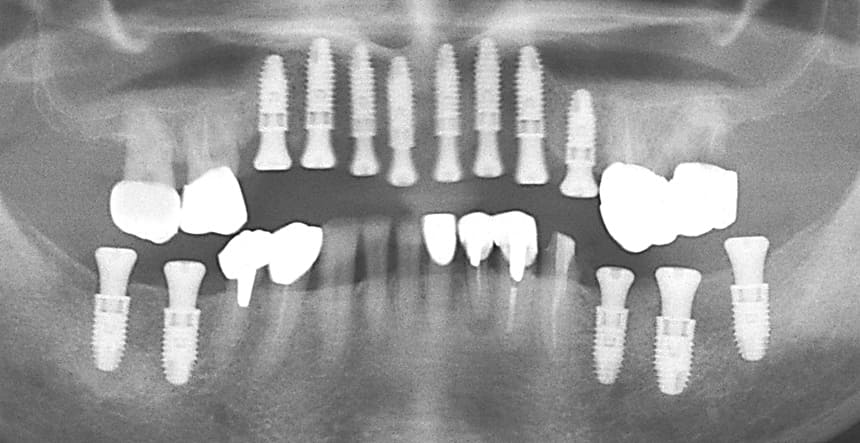

上顎にインプラント8本を埋入した術後のパノラマXP所見:上顎骨に対するインプラントの長さに関しては12mm-10mmが適切であり前歯部では12mmを小臼歯部では10mmを選択している。また左下のブリッジに関しては温存できなかった第2大臼歯が抜去されている。

上顎のインプラント埋入後約1か月で、両側下顎臼歯部にインプラント埋入を行った。左下のインプラント埋入では小規模の骨増生を伴うインプラント埋入を行った。

両側下顎臼歯部に対してのインプラントについては8mmから10mmが選択されるが骨量が十分あったことから10mmを選択して埋入した。左側の小臼歯部では水平的骨が若干、不足しているためドリリング時に採取された自家骨を骨増生として利用した。

上顎前歯部と両側小臼歯部はインプラント補綴を行い、両側の大臼歯部についても根管治療からやり直して咬合平面を改善すべく補綴を行った。下顎の両側臼歯部に関してもインプラント補綴を行い小臼歯部では根管治療からクラウンによる補綴を行った。左上7番に関しては当初インプラント補綴を行う予定であったがサイナスリフトを伴う治療になることと第一大臼歯までで十分噛めることから埋入せずに経過を見ている。

治療後の口腔内所見である噛み合わせも問題なく機能している。また、一本ずつのインプラント補綴を行ったことでフロスによるケアができ良好な口腔内環境を維持できている。